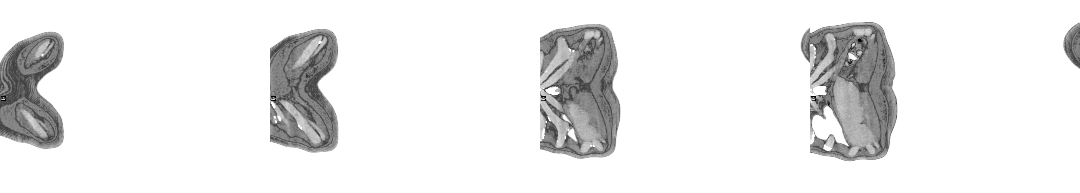

The moment I saw the very first scan the doctors showed me (bottom right, above: an MRI, rather than PET, as it happens)—on a small monitor wheeled into my cubicle at the Homerton—seemed to say everything at once. As I turned my head to look at the image of my brain on the monitor, I glimpsed also the tattoo on my left arm suddenly aligned with it (bottom left)—a tattoo of a bhikkhu meditating in flames, inked twenty years earlier, with the bhikkhu meditating as descibed in the Buddha’s Adittapariyaya Sutta (Fire Sermon)—such that the tattoo of the bhikkhu and the scan of the brain, aligned properly. One presaged the other by years, holding out its hand to the other. They reflected each other so neatly, with the tumour in the cerebellum showing up as the red-orange fire bursting through from within, which the bhikkhu sits through.

The wrinkled surface of the cerebral cortex in the scan echoed the Bhavachakra—the wheel of Saṃsāra, of cyclical existence (“Saṃsāra… is a Sanskrit word that means ‘wandering’ as well as ‘world’, wherein the term connotes ‘cyclic change’ or, less formally, ‘running around in circles’)10—against which the bhikkhu rests in the tattoo. Here is an image, not only of that empty time turning that we have talked of, of cyclical return and, dare I say it, reincarnation (though in this formulation, reincarnation is mere repetition, as in the ‘natural’ repetition of pagan society). In the original Fire Sermon, the argument is that the bhikkhu must free themself from the grasping tyranny of the senses. We, on the other hand, will be moving in the other direction. In any case, this combined image almost made me fall out of bed.